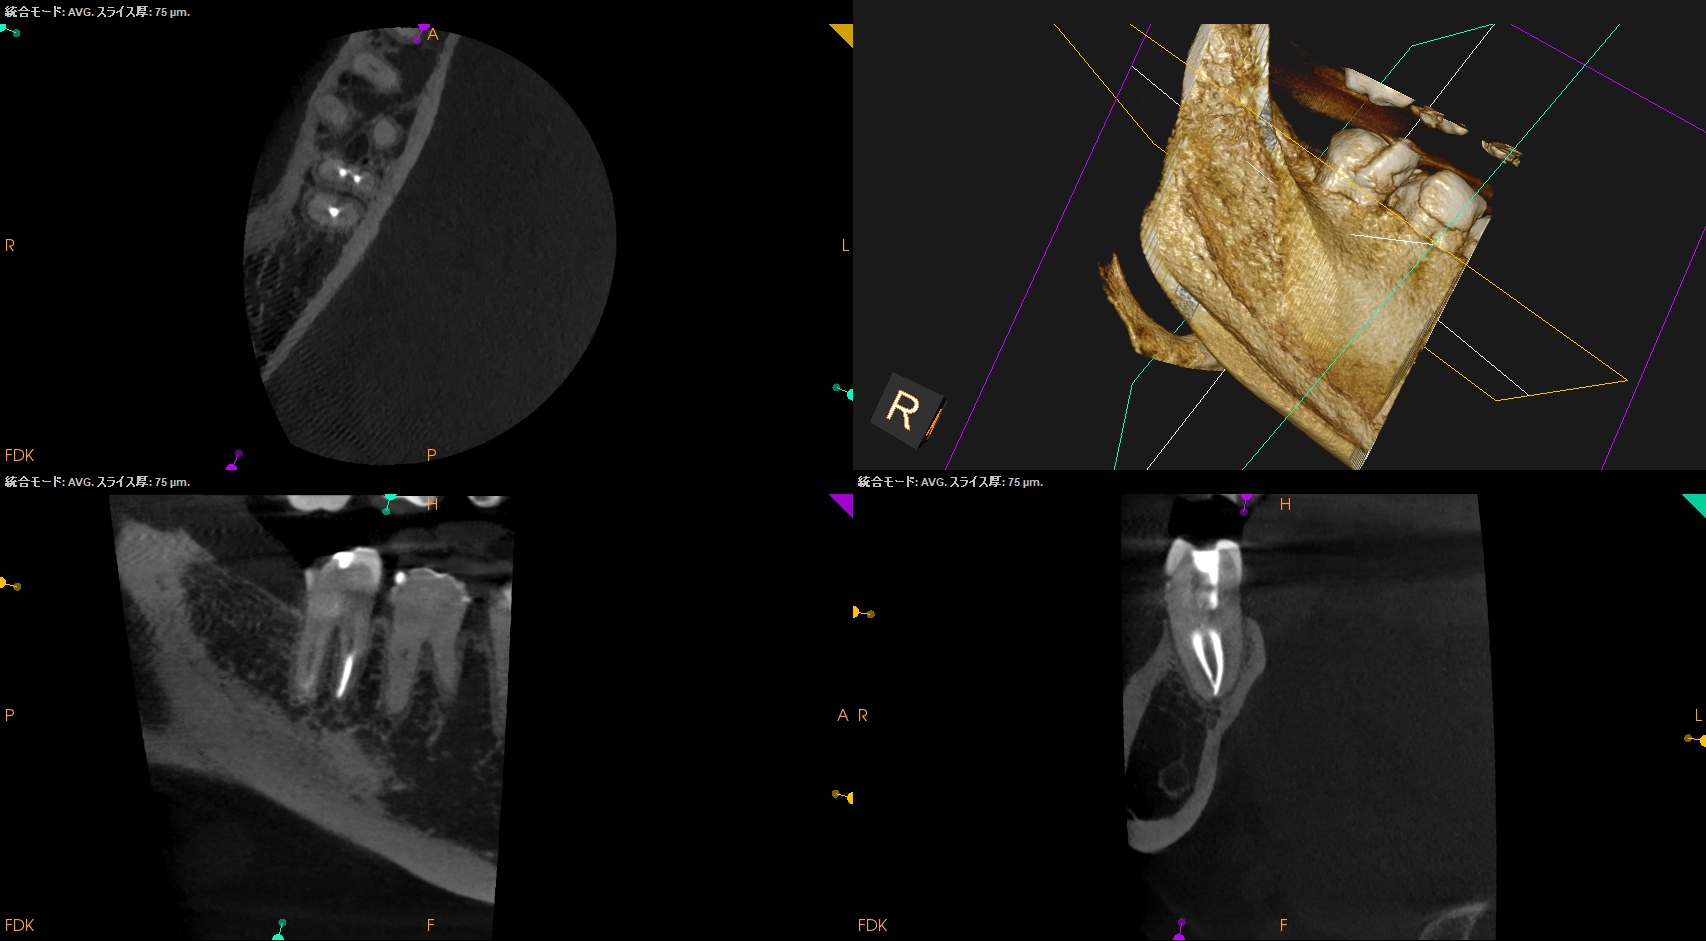

術後にPA, CBCTを撮影した。

MB

ML

D

問題はないだろう。